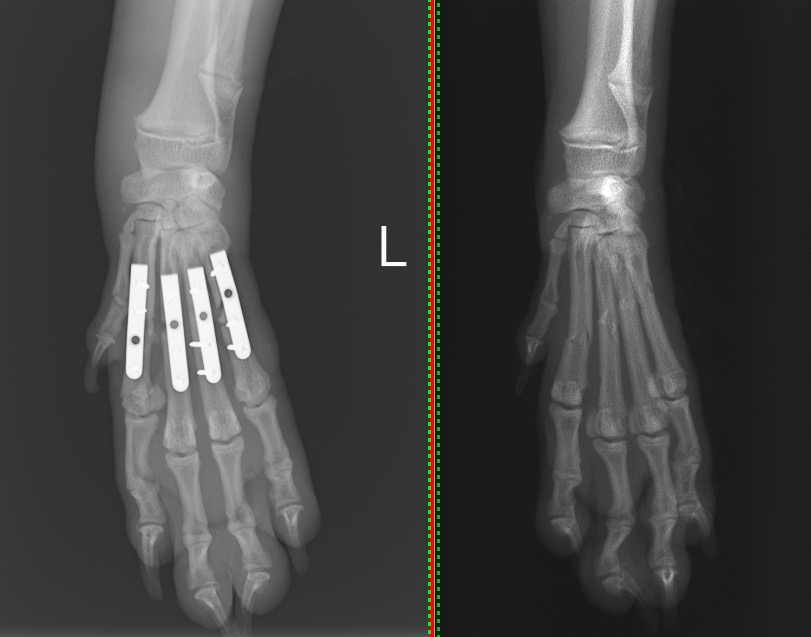

犬の中手骨骨折(1.1mmプレート使用) 左:術後/右:術前